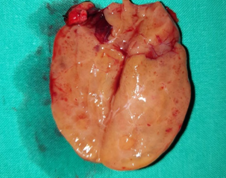

Purple arrow: over-descended large superior parathyroid adenoma. Yellow arrow: normal right inferior parathyroid gland found in the thymothyroid ligament (Courtesy Dr. V. Penopoulos)